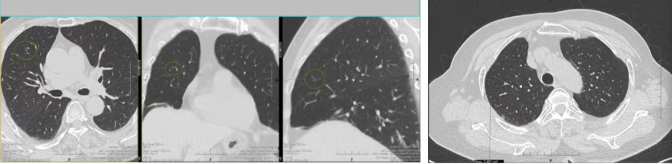

患者因常规体检发现右肺上叶多发结节前来我院就诊。完善胸部CT等相关检查后,影像显示其右肺上叶存在4枚大小、形态均有差异的结节,分布位置较为分散,且多枚结节具备恶性病变的高危特征。若按照传统诊疗模式,此类多发结节往往需分次手术切除,患者不仅要承受多次麻醉、多次手术切口的痛苦,还会面临住院周期延长、治疗费用增加的问题,同时反复手术会对肺功能造成累积性损伤,进一步加重身心负担。

接诊后,杨跃教授团队结合患者影像学资料、身体基础状况进行全面评估,精准研判每一枚结节的位置、潜在风险与病理性质。针对结节分布分散、恶性概率高的特点,团队最终制定出胸腔镜下精准定位+同步切除的个体化手术方案,计划通过单一微创切口,一次性完成4枚结节的完整切除,既实现病灶根治,又最大限度保留正常肺组织,助力患者术后快速康复。

手术当日,在麻醉科、手术室团队的紧密协作下,杨跃教授主刀,凭借娴熟的腔镜操作技术,在狭小的胸腔空间内精准定位每一枚结节,细致分离周围组织,避开血管与支气管,稳步完成4枚结节的切除。术中快速病理结果与术前评估高度一致,确认3枚结节为肺腺癌、1枚为癌前病变,手术切除范围精准、彻底,达到了根治性治疗。